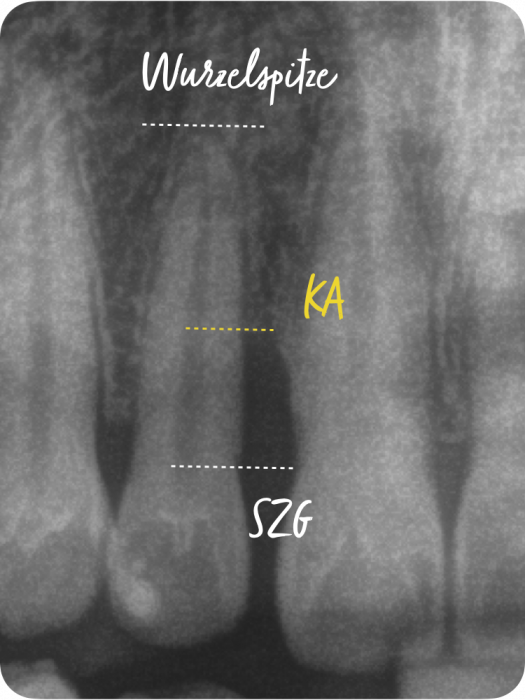

Der Grad enthält Informationen zur Progressionsrate der Erkrankung und dem Vorliegen von patientenspezifischen Risikofaktoren (Nikotinkonsum und Diabetes/HbA1c). Die Progressionsrate kann direkt anhand von Vorbefunden abgeschätzt werden oder indirekt durch den sogenannten Knochenabbauindex (KA %/Alter). Dabei wird der Zahn auf dem Röntgenbild berücksichtigt, der den stärksten marginalen Knochenabbau hat. Das Vorliegen von Risikofaktoren kann zu einem Upgrade führen. Fehlen diese Risikofaktoren, führt das aber nicht zu einem Downgrade.